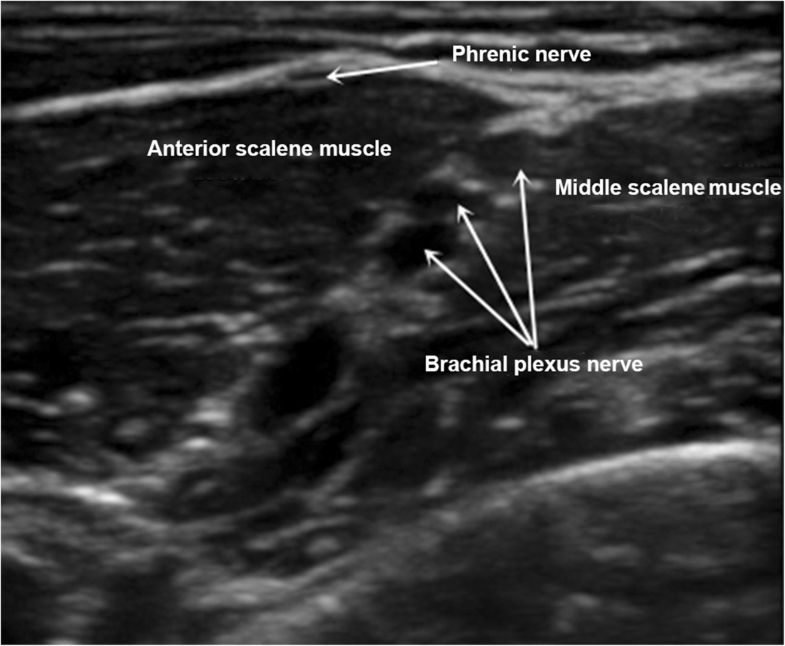

Ultrasound